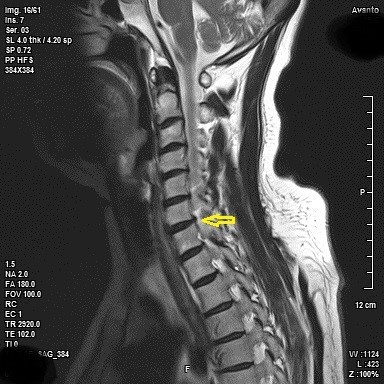

목디스크 증상 목디스크란 목 뼈 사이의 디스크가 원래의 자리에서 이탈하면서 신경을 누르거나 뼈조직이 비정상적으로 자라나 목을 지나가는 척추신경을 누르게 됨으로써 통증을 느끼는 질환입니다. 예전에는 40대 이상의 분들한테서 주로 나타나는 질환이었지만 요즘은 젊은 세대에도 흔하게 볼 수 있는 질환이 되었습니다.

목디스크가 심한 해당에는 어깨뿐만 아니라 팔과 손가락에도 저림을 동반한 고통을 느끼실 수 있다. 디스크의 수핵이 빠져나가거나 퇴행성 경추 척추증 및 경추관 협착증 등으로 척수가 눌리게 되면 대개는 팔의 힘이 빠지는 느낌을 받을 수 있다. 이러한 해당에는 팔을 머리 위로 들면 고통이 완화되는 해당이가 있는데 일시적일 뿐 목디스크의 전형적인 증상이니 꼭 정형외과에 방문하셔서 전문의에게 상담을 받아보시길 권장드린다.

목디스크 치료방법 중 수술치료 방법은 비수술적 치료가 효과가 없거나 디스크 신경 압력이 너무 높을 때 최후의 수단입니다. 사소한 치료조차 할 여지가 없습니다. 즉. 비수술적 방법을 고집하더라도 주변 정상 조직이 손상될 수 있습니다.

치료 방법에는 인공 대체물로 디스크 교체, 척추 유합술 및 전방 감압 및 유합 수술, 신경 감압 수술, 후궁 절제술 및 후궁 성형술이 있습니다. 무엇이든 치료하기 전에 전문가와 상의해야 해요. 적절한 진단이 우선되어야 합니다. 그리고 전문의와 상의 후 구체적인 치료법을 결정해야 해요.